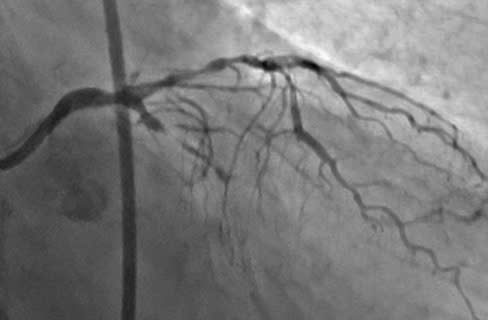

Kết quả chụp động mạch vành cho thấy động mạch liên thất trước (nhánh mạch máu quan trọng nhất của tim) bị hẹp khít tới 90%. Động mạch vành mũ đã bị tắc hoàn toàn mạn tính (CTO). Điều này đồng nghĩa với việc hai trong ba nhánh chính nuôi tim đều bị tổn thương nghiêm trọng, đẩy trái tim vào tình trạng thiếu máu nuôi dưỡng có nguy cơ cao dẫn đến suy tim nặng, thậm chí tử vong bất cứ lúc nào.

Dưới sự dẫn đường của hệ thống chụp mạch xóa nền kỹ thuật số (DSA), đội ngũ bác sĩ đã phối hợp chặt chẽ, sử dụng các dụng cụ chuyên biệt gồm dây dẫn siêu nhỏ và siêu cứng (guidewire) với sự hỗ trợ của các vi ống thông (microcatheter) để tiếp cận và đưa dây dẫn qua vị trí tắc mạn tính của động mạch vành mũ. Sau đó, các bác sĩ đã đặt 01 Stent tái thông động mạch mũ một cách an toàn.

Hình ảnh sau đặt Stent động mạch mũ

Toàn bộ ca can thiệp diễn ra trong 45 phút căng thẳng, đòi hỏi kỹ năng chuyên sâu, sự phối hợp nhịp nhàng và tập trung cao độ. Kết quả, nhánh động mạch mũ tắc hoàn toàn mạn tính đã được tái thông hoàn toàn, phục hồi dòng máu nuôi dưỡng cơ tim, chấm dứt các triệu chứng thiếu máu cơ tim và mở ra cơ hội sống cho người bệnh. Sau can thiệp, bệnh nhân hết đau ngực, không khó thở, các chỉ số sinh tồn ổn định và được xuất viện chỉ sau 4 ngày điều trị.